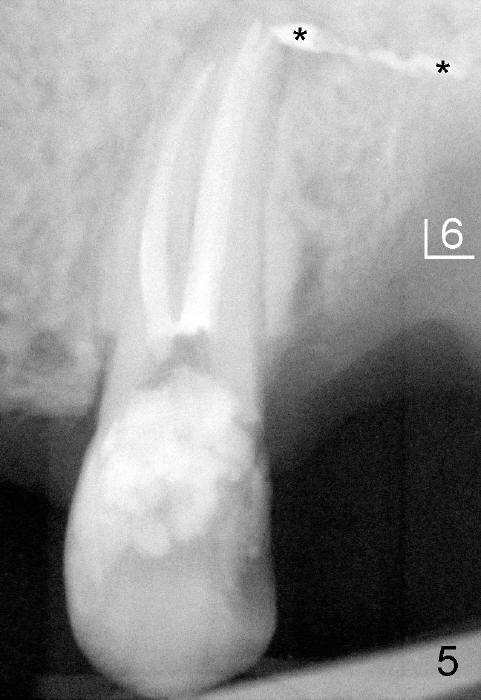

上颌第一前臼齿一般有两个根管(颊侧,鄂侧),偶尔上颌前臼齿有三个根管,可发生于第一或者第二(本例),病人二十四岁,黑人,男,左上第二前臼齿(图一:5)髓腔(*)好像分成三个根管(箭头),仔细观察显示根尖也有三个(图二(图一放大)彩色轮廓与第一磨牙三个根对比:近中颊侧(MB),远中颊侧(DB),鄂侧(P))。因此有三个根管的前臼齿好像小型磨牙,不过颊侧两个根融合。

开髓时发现颊侧(图三B)髓腔比鄂侧(P)宽,根管口分布与上颌磨牙不差上下(图四),图三图四是镜影像。图五显示根管充填后:三个牙胶尖;AH26 Plus 糊剂超填(*),基本在第一磨牙牙槽窝(6)近中,第一磨牙两个月前拔除。根管治疗完成后九天糊剂(图六*)转移到第一磨牙牙槽窝远中,说明牙槽骨象蜂窝,糊剂,细菌自由来往,植牙周围不应该有感染。